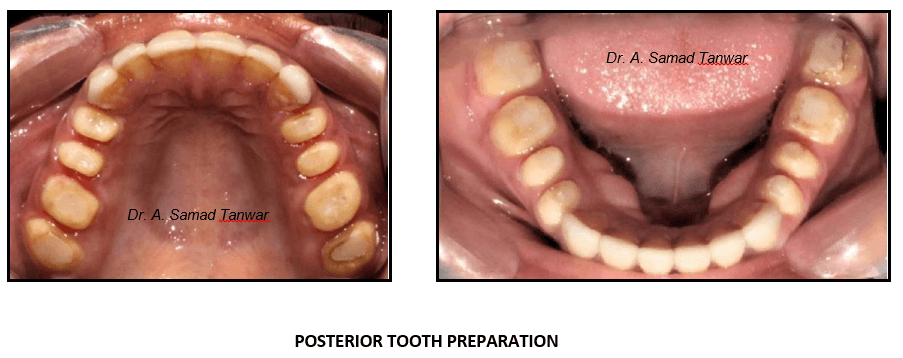

Posterior tooth preparations were completed to receive Porcelain fused to Metal restorations.

Double mix double step impressions were made using PVS elastomeric impression material

Occlusal view of the restorations In-situ